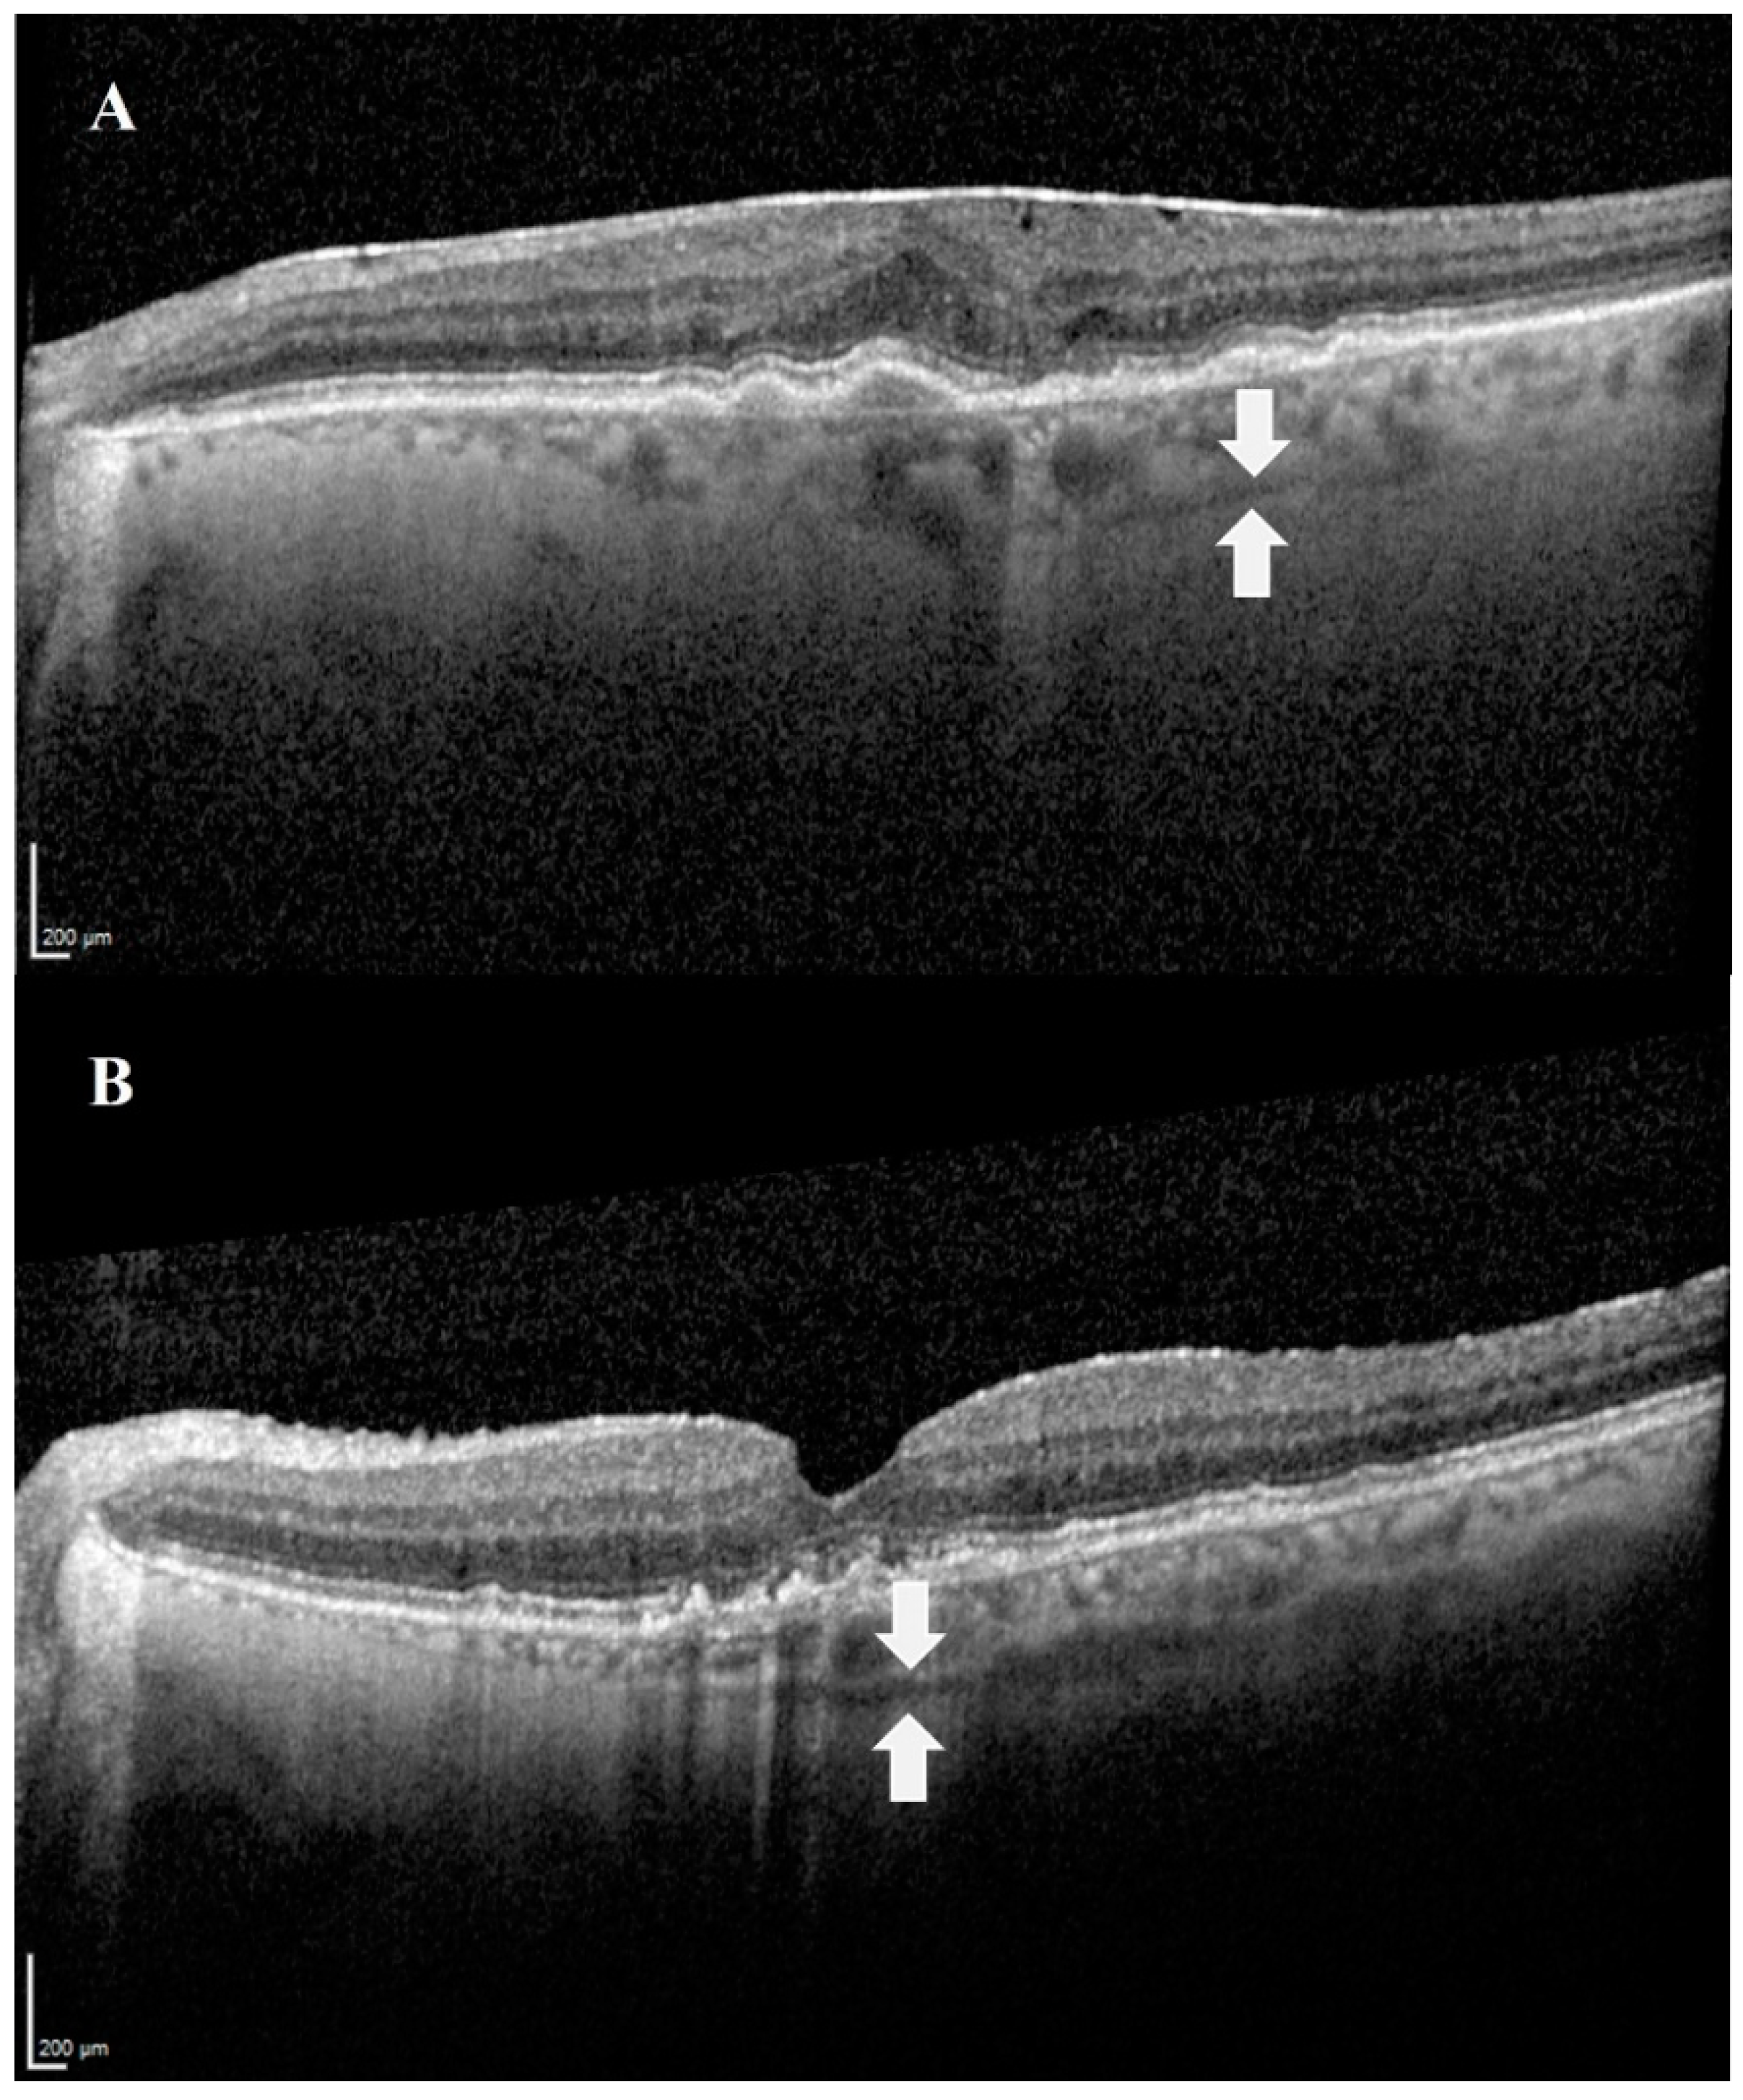

- Hanhart, J.; Rozenman, Y. Optimized imaging of the suprachoroidal space with swept-source OCT. Asian J. Ophthalmol. 2019, 16, 323–328. [Google Scholar] [CrossRef]

- Michalewska, Z.; Michalewski, J.; Nawrocka, Z.; Dulczewska-Cichecka, K.; Nawrocki, J. Suprachoroidal layer and suprachoroidal space delineating the outer margin of the choroid in swept-source optical coherence tomography. Retina 2015, 35, 244–249. [Google Scholar] [CrossRef]

- Kim, J.H.; Chang, Y.S.; Kim, J.W.; Lee, T.G.; Lew, Y.J. Imaging Suprachoroidal Layer in Exudative Age-Related Macular Degeneration. Curr. Eye Res. 2016, 41, 715–720. [Google Scholar] [CrossRef]